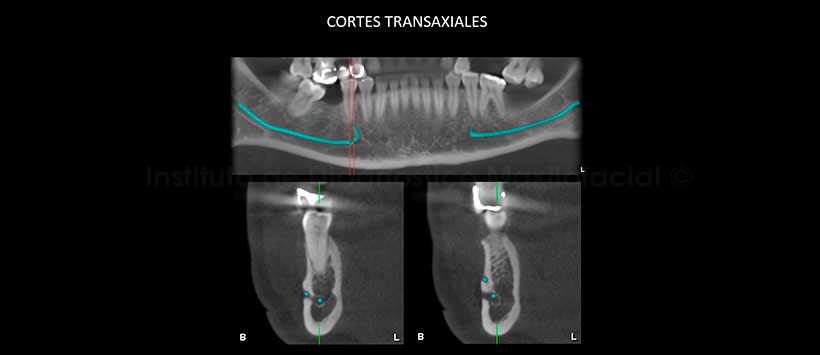

La tomografía computarizada de haz cónico, mediante los cortes transaxiales y tangenciales, muestra claramente la presencia de dos agujeros mentonianos en un mismo lado, en este caso en la parasínfisis mandibular del lado derecho; además, de su distribución a nivel de la tabla ósea bucal (Fig. 2 y 3).